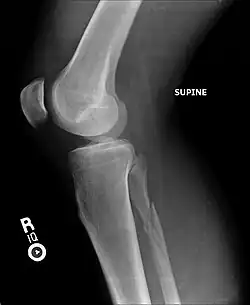

Fracture of the lateral malleolus seen on X-ray scan (left ankle)

The Maisonneuve fracture generally follows a specific pattern of injury. The following are described as subsequent events that result in a Maisonneuve fracture:[3][4][12]

• Forceful, external rotation of the ankle joint results in the tearing of the deep deltoid ligament and/or an avulsion fracture of the medial malleolus.

• The ankle mortise is subjected to excessive torque, rupturing the syndesmotic ligaments and anteromedial ankle joint capsule.

• Rotative energy is transferred upwards along the interosseous membrane, damaging it in the process.

• The force results in a spiral, sometimes an oblique, fracture at the neck of the proximal fibula.

In cases where the anterior aspect of the tibiofibular syndesmosis can resist mechanical stress, only an oblique fracture of the lateral malleolus is produced. Diastasis of the lateral malleolus may also occur, in which it is posterolaterally displaced from the tibia.[9]